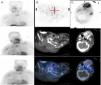

Parathyroid scintigraphy: (A) Planar imaging of head and chest in the anterior projection following administration of 20mCi of 99mTc-MIBI (methoxy isobutyl isonitrile) at 20, 60, and 180min, showing increased uptake of the radiotracer next to the lower half of the left thyroid lobe, which was sustained during the long period of examination. (B) Selected axial section of the SPECT/CT image at 60min, SPECT/CT fusion showing a focus of increased uptake of retrotracheal location somewhat to the left, up to D1. Findings are consistent with parathyroid adenoma or hyperplasia. (C) Selected axial section of the SPECT-CT image, based on skull and jaw region. The SPECT, CT, and fusion images show a large area of irregular increased uptake of radiotracer in left maxilla, appearing as expansive osteolytic lesion in the CT scan and consistent with a brown tumour.3